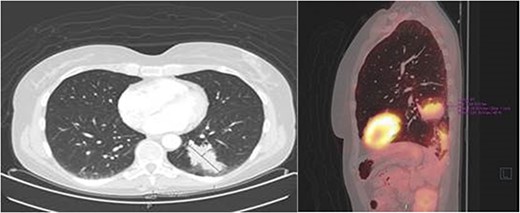

Histopathological examination of the biopsy showed an adenocarcinoma metastasis of rectal origin. A full body positron emission tomography (PET)-scan and MRI were made and confirmed the vaginal lesion of 1.7 × 1.4 × 1.5 cm located in the posterior wall of the vagina just above the puborectal sling (see Figs 1 and 2). From the histopathological and imaging diagnostics we concluded that the patient had a distal rectovaginal septum metastasis of rectal origin.

After 1 month of initial diagnosis, an excision of the tumour was performed through open approach with primary closure of the vaginal wall. Histopathological examination confirmed the solid tumour to be metastatic disease from rectal origin with free margins. The newly discovered symptoms related to the rectovaginal septum metastasis had completely disappeared following the excision. Upon further follow-up at 2 years and 6 months; routine lab results showed a significant increase in the CEA levels at 5.2 ug/l (3 months prior at 4.0 ug/l). Given this significant increase; a PET-scan was again performed. The PET-scan revealed a lesion within the left lower lobe of 5.7 cm in a transverse plane; suspected to be distant metastasis (see Fig. 3). Compared to the last PET-scan, this lesion was a new development not previously seen. CT-guided thoracic biopsy confirmed by histopathological examination, that this lesion was indeed a distant metastasis of the previous rectal cancer.

Transverse- and sagittal plane of the PET-scan showing a leasion in the left lower lobe with metabolic activity.